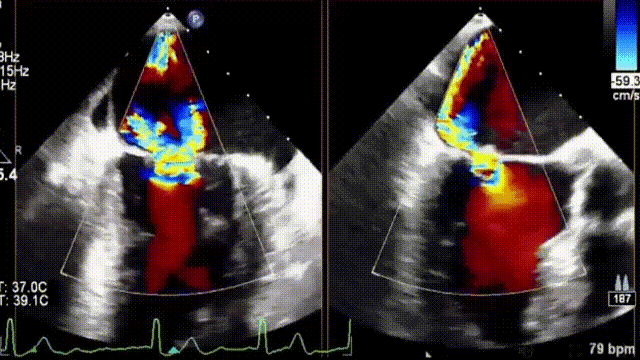

术前,宋光远教授团队对患者基本情况进行反复研究,确定患者不适合外科开胸手术,遂决定选择微创的经导管二尖瓣夹合术。术中经股静脉入路,在超声介导下成功完成房间隔穿刺并建立导丝路径。随后,宋光远教授通过信息采集机器人的高清摄像设备清楚展示了MitraClip系统手术器械的准备过程,对Clip、SGC、CDS及固定装置进行排气及体外调试,以及后续的手术过程。由于患者左前降支存在严重狭窄且合并房颤,如何保障患者围手术期血流动力学稳定是完成手术的重要难题。在食道超声及X线引导下,应用两个MitraClip的二尖瓣夹反复调整夹取位置,最终成功捕获并夹合返流严重部位,使二尖瓣在收缩期由大的单孔变成小的双孔,从而减少二尖瓣返流。二尖瓣夹释放后,超声显示返流几近消失,患者各项生理指标正常。

术后彩超提示返流几乎消失